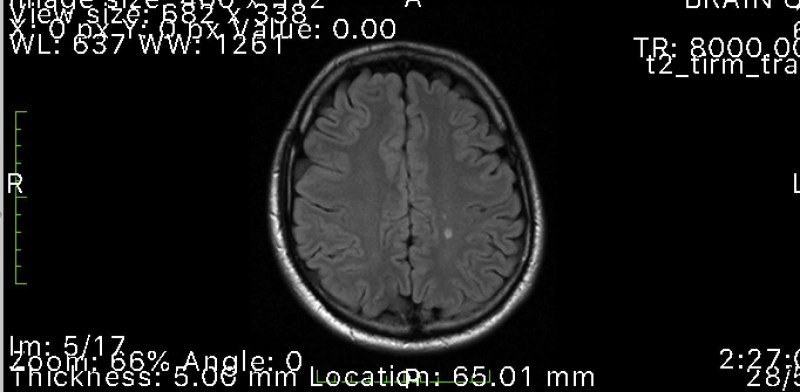

Ironically, the day after writing my neuro-optometry review, Josh sent me his MRI scans. He appeared to have a couple of demyelinating lesions typical of MS, which were confirmed by both the GP and his neurologist. The neurologist then arranged for a lumbar puncture and confirmed the diagnosis of MS, prescribing Josh oral tecfidera capsules, which thankfully for Josh were also covered by Medicare. All this took place before Josh manifested any signs of MS so he is very grateful.

Fig 2. MRI scan showing demyelinating lesions typical of MS